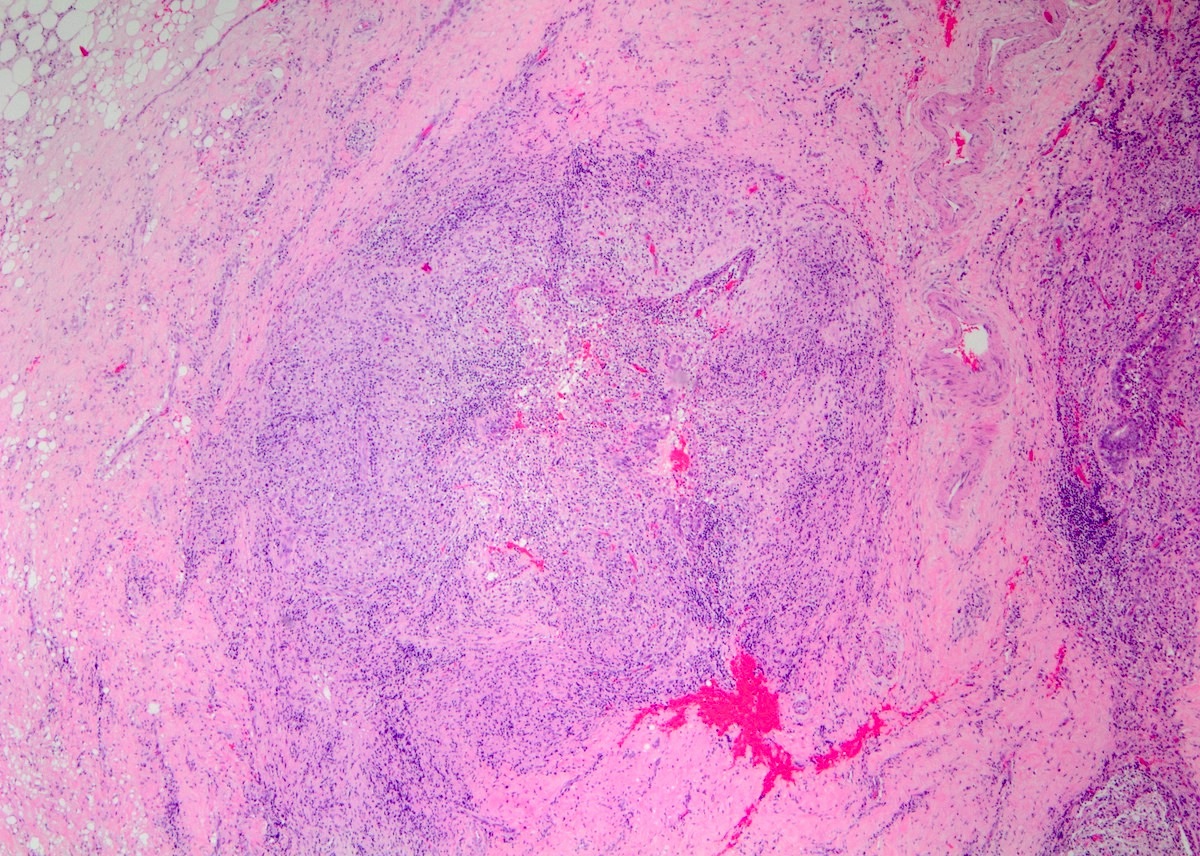

Microscopic (histologic) description

- Lobulocentric granulomatous inflammation (Pathology 2004;36:254)

- Granulomas often contain neutrophils

- Neutrophils can create microabscesses; overlapping features with cystic neutrophilic granulomatous mastitis

- Multinucleated giant cells, lymphocytes, plasma cells and eosinophils within and around lobules

- Extensive inflammation might obliterate lobulocentric distribution

- Caseous necrosis not present

- Schauman and asteroid bodies not common

Microscopic (histologic) images